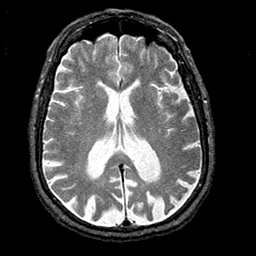

Alzheimer's disease MR T2-weighted -- Slice #27

[Home][Help][Clinical][Tour 1][Tour 2] Slice 27